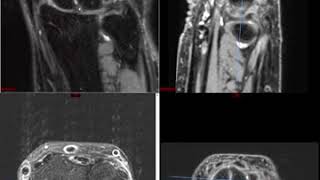

Textbooks can't teach you how to read a scan. This channel bridges the gap between theory and practice.

I'm Rajesh, a radiologist in Toronto. I created this channel to give you the practical, real-world radiology training I wish I had as a resident.

That’s why we built the platform on NavigatingRadiology.com -- an interactive system with a full screen PACS viewer, curated high-yield courses, and an “AI Attending” that gives you instant feedback and guidance.